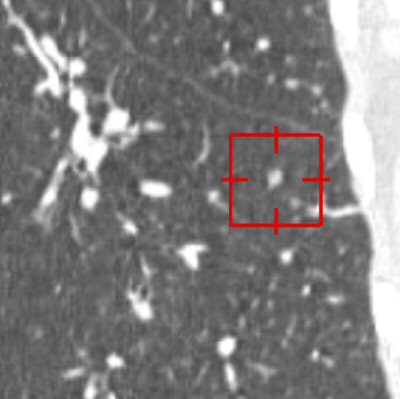

| An elongated nodule missed by all three radiologists during free search. On the axial image (above), the small nodule looks more likely to be a vascular structure with an elongated shape and parallel orientation with adjacent branching vessels. On the coronal image (below), the lesion seems more globular in the craniocaudal direction. 3D volume-rendered image (bottom) presents a discrete nodule between vessels. Although this true-positive nodule was detected by CAD, all three radiologists rejected this nodule with low confidence scores. All images courtesy of Dr. Chin Yi. |